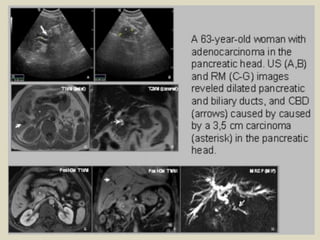

Pancreatic carcinoma A 59 years old men presented with painless jaundice over past

several days. Contrast enhanced CT (with multiplanar and MIP reconstructions) showed:

(a) intra hepatic dilated bile ducts. (b) the ‘double duct’ sign with dilatation of both the

CBD and pancreatic duct (arrows) and distension of the gallbladder. (c,d,e,f,g) irregular

pancreatic head mass with heterogeneous enhancement and central necrosis.

Pancreatic carcinoma A59 years old men presented with painless jaundice over past several days. Contrast enhanced CT (with multiplanar and MIP reconstructions) showed: (a) intra hepatic dilated bile ducts. (b) the ‘double duct’ sign with dilatation of both the CBD and pancreatic duct (arrows) and distension of the gallbladder. (c,d,e,f,g) irregular pancreatic head mass with heterogeneous enhancement and central necrosis.